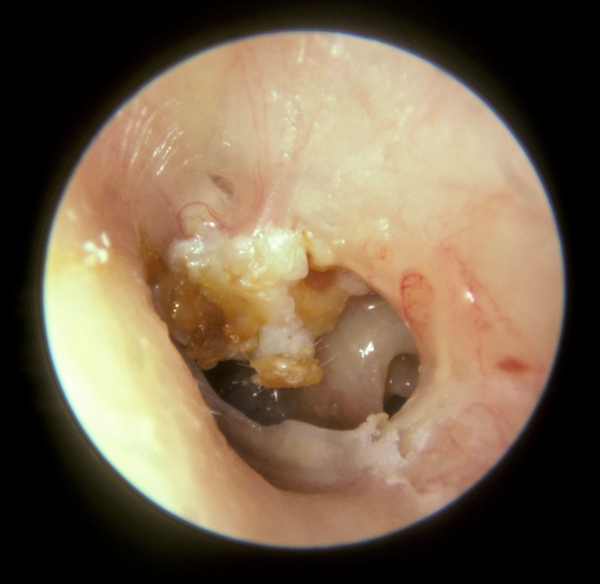

Cholesteatoma with perforated tympanic membrane.

• Cystic, 1-4 cm diameter lesion within the middle ear canal that derives from a nest of keratinized squamous epithelial overgrowth or mucus-secreting epithelium.

• If the inflammatory medium surrounding the cholesteatoma becomes severe enough, it may erode into the ear ossicles and cause conductive hearing loss.

• Photograph by Michael Hawke, MD